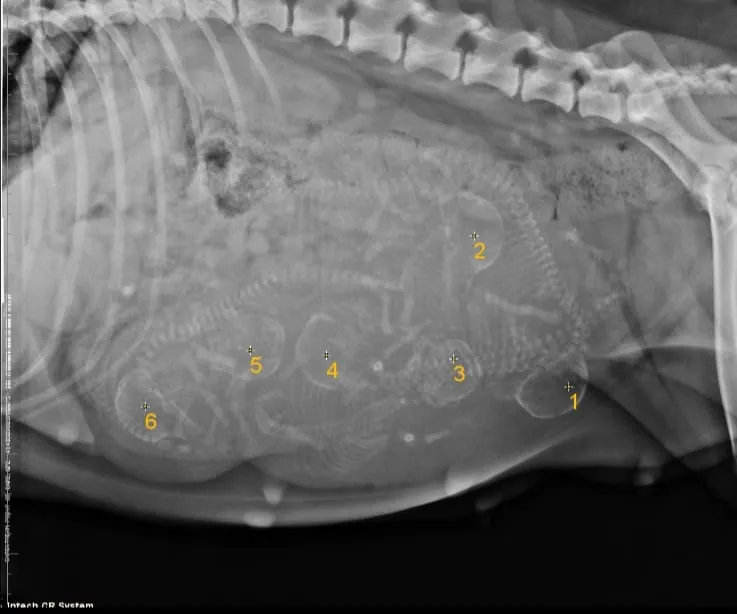

7th of March 2023. our beautiful Gaga gave birth to 6 stunning puppies, 5 boys & 1 girl.